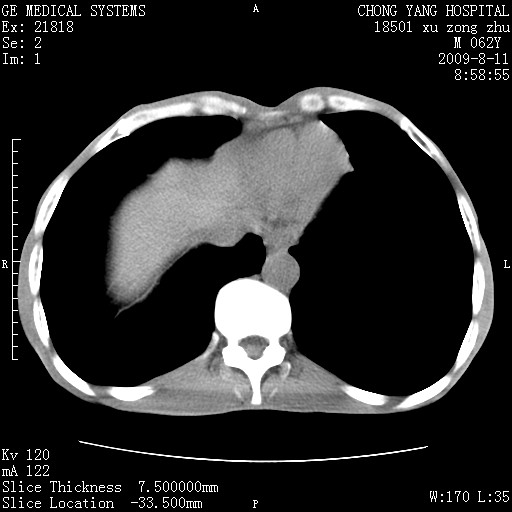

以下是引用杀毒软件在2009-8-11 16:35:00的发言:[br]肝内胆管扩张局限于左叶,胆管内有结石伴肝外胆管结石,胆管壁增厚呈弥漫性并发腹腔积液,胰腺边界模糊。[br][br]考虑---胆总管及肝内胆管结石继发胆管炎及胰腺炎,左肾下极囊肿,腹水。

以下是引用zjzjr在2009-8-11 17:35:00的发言:[br]肝内胆管扩张局限于左叶,胆管内有结石伴肝外胆管结石,胆管壁增厚呈弥漫性并发腹腔积液。[br][br]考虑---胆总管及肝内胆管结石继发胆管炎,左肾下极囊肿,腹水。